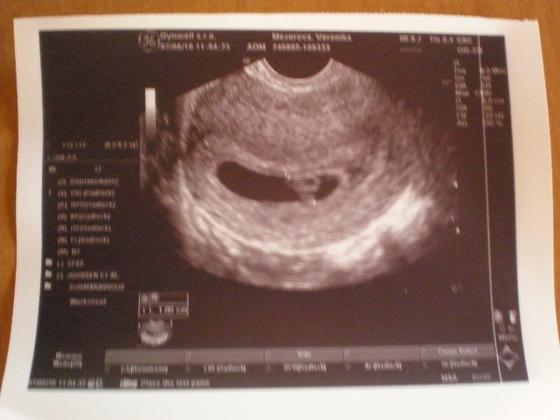

2.6. jsem šla na druhý ultrazvuk a plná nervů zda bude srdíčko ... srdíčko bušilo jak o zavod a ja slzy na krajíčku 🙂 je to nadherný pocit 😀 dostala jsem prukazku i druhou fotečku 🙂 jsme 7+1